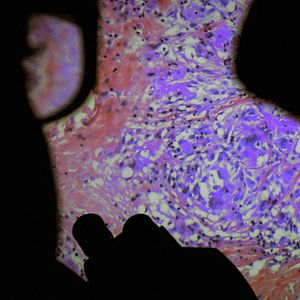

Filmado em cinco hospitais franceses nos bairros do norte de Paris, ao longo de vários anos com uma câmera especialmente projetada, este documentário revela que a carne humana é uma paisagem extraordinária que existe apenas através do olhar e da atenção dos outros.